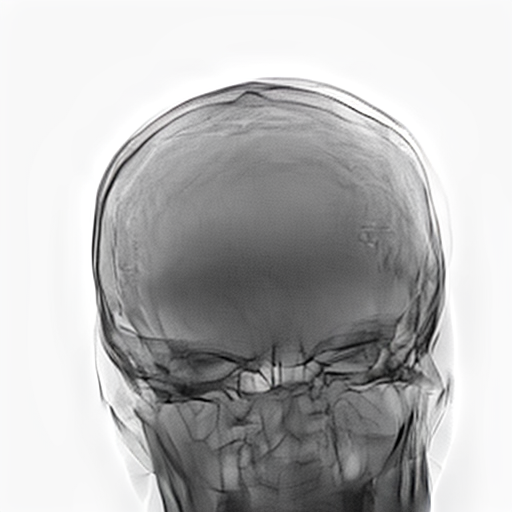

Refer to caption

Figure 2: Dataset overview. The synthetic domain contains Low and High dosage samples generated using the Mentice VIST® simulator; the real domain includes Low, Normal, and Exposure dosage categories acquired from a skull phantom using the Philips Azurion IGT system.

We develop and release a new dataset of real and synthetic head X-ray images, X-DigiSkull, to study the domain adaptation. The dataset consists of synthetic X-ray images of a human skull generated using the Mentice VIST® simulator 111https://www.mentice.com/simulator/vist-g7. Real‑time X‑rays are generated by holding the 3D voxel “patient” head model with per‑voxel attenuation, casting one ray per detector pixel to form a digitally reconstructed radiograph and then approximating scatter, focal‑spot and detector blur, grid/heel effects and detector response, adding quantum/read noise and final image post-processing as the C‑arm and devices move. Real images are acquired from a clinical-grade physical skull phantom using the Philips Azurion Image Guided Therapy (IGT) system. Images are captured from common IGT working positions for neuro procedures. The dataset consists of multiple orientations and is available in three different radiation dose settings: low, normal, and exposure (Philips exclusive), the latter offering enhanced image quality and detail, as shown in Figure 2. This consists of viewing angles rz[40,+40]r_{z}\in[-40^{\circ},+40^{\circ}], ry[40,+40]r_{y}\in[-40^{\circ},+40^{\circ}], rx[40,+40]r_{x}\in[-40^{\circ},+40^{\circ}] with respect to the starting position in 10 increments and up to 3 images at each position to capture the noise present. This results in a total of 2,187 real images. The coordinate systems of the real and synthetic environment are aligned and synthetic images are rendered to approximate the same viewpoints as the real phantom images with the patient table starting at a similar position.The head 3D model used in the simulation is meticulously built from a real clinical case. We capture the synthetic images in finer increments of 5 across the three angles, producing the 5,832 (18318^{3}) images 222Data available at https://zenodo.org/records/16535437. The aim of this alignment is not to achieve precise supervised image translation, but rather to establish a consistent reference structure that preserves spatial features. The composition of the dataset is summarized in Table 1, which contains information on the splits and the number of images available. All images are cropped and resized to 780×\times780 pixels. The test set is obtained by uniformly sampling 15% of viewing angles and corresponding images to ensure a representative distribution. For our experiments, we focus on the task of converting synthetic images at high dose to real images at normal dose.